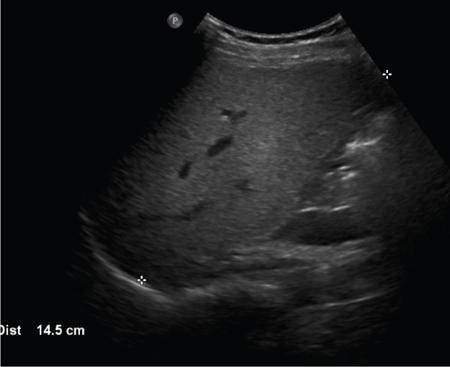

Ritu K. Kashikar, Shrinivas B. Desai Knowledge regarding normal dimensions of organs is important as visceromegaly is the first and often only abnormality in a variety of disorders. The radiologist should also be aware of normal diameters of vessels and ducts because an increase in size is usually a pointer to pathology in the organ. This chapter is a lucid review of normal sizes of organs, vessels, duct and also focuses on which section and location should size be measured to avoid interobserver variation. The liver is the largest organ in the abdomen. Hepatomegaly is a common condition and often the first clinical and imaging feature of various disorders. It is hence imperative for the radiologist to know the normal size and the section on which measurements should be taken. USG is commonly used to measure liver size. The longitudinal view is commonly used to measure liver size. The liver is considered normal in size if on longitudinal scan through the midhepatic line the liver measures 13 cm or less. This is true in approximately 93% individuals Measurement more than 15.5 cm suggests hepatomegaly in 75% cases (Figs. 9.3.1 and 9.3.2) (Table 9.3.1). Hepatomegaly is also suggested by an inferior angle of more than 45 degrees in the left lobe and more than 90 degrees in the right lobe. The normal liver measures approximately 6.5 cm first 3 months of age and reaches a size of 12.5 cm by 10–12 years of age. Liver size can be measured on unenhanced or enhanced CT. On CT the liver measures 10–12.5 cm in the midclavicular line on an average. A liver measuring more than 15.5–16 cm in the midclavicular line is considered enlarged. The midclavicular line measurement is done in coronal plane (Fig. 9.3.3). Another important measurement is the size of caudate lobe. The caudate to right lobe ratio (C/RL) is a measurement used to diagnose caudate lobe hypertrophy and right lobe atrophy which is important in the diagnosis of cirrhosis. The axial section immediately below main portal vein bifurcation is used for measurements. The following lines are drawn on the liver (Fig. 9.3.4). C/RL: In an adult patient of average weight (60 kg), the estimated liver volumes can range from 1024–1302 cm3 (Fig. 9.3.6). USG and Doppler provide important information regarding patency of artery in postoperative/transplant setting. Normal hepatic artery waveform is pulsatile and of low resistance. The normal resistive index measures 0.7. High or low resistivity index (RI) indicated pathology. The measurements of the hepatic arteries bare importance in transplant imaging. The diameter and length of the arteries are best measured on CT angiogram images. Arteries smaller in calibre than 2 mm may be difficult to anatomize. Replaced RHA is often longer in length than standard arteries. The normal diameters of the hepatic arteries are mentioned in Table 9.3.2 (Figs. 9.3.7–9.3.9). The portal venous system is valveless and hence its diameter is influenced by respiratory variations. The portal venous diameter is greatest during inspiration and hence all measurement should be made in this phase (Table 9.3.3). The diameter of portal vein has importance in diagnosing portal hypertension and USG is often used for this purpose. USG also provides other important parameters like flow velocity and volume flow which are relevant in the setting of portal hypertension. The normal portal venous velocity measures 15–18 cm/sec.(Fig. 9.3.10)

Normal usg measurements

Midclavicular line

The normal liver measures 10.5 ± 1.5 cm in longitudinal diameter and 8.1 ± 1.9 cm in the anteroposterior projection

Midline

Normal liver measures 8.3 ± 1.7 cm (95th percentile = 10.9 cm) and 5.7 ± 1.5 cm (95th percentile = 8.2 cm) in longitudinal and anteroposterior dimensions